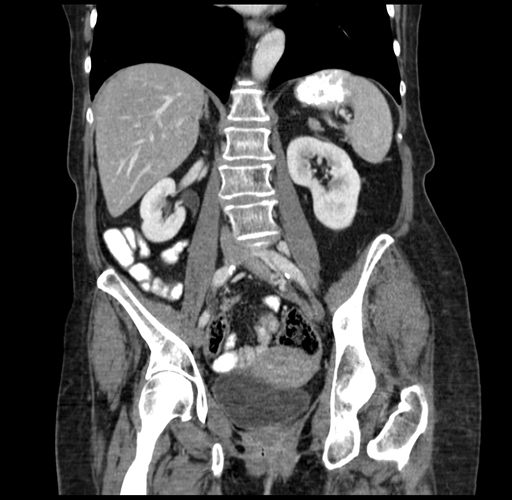

Pre-Chemo: Coronal Venous

Coronal Venous